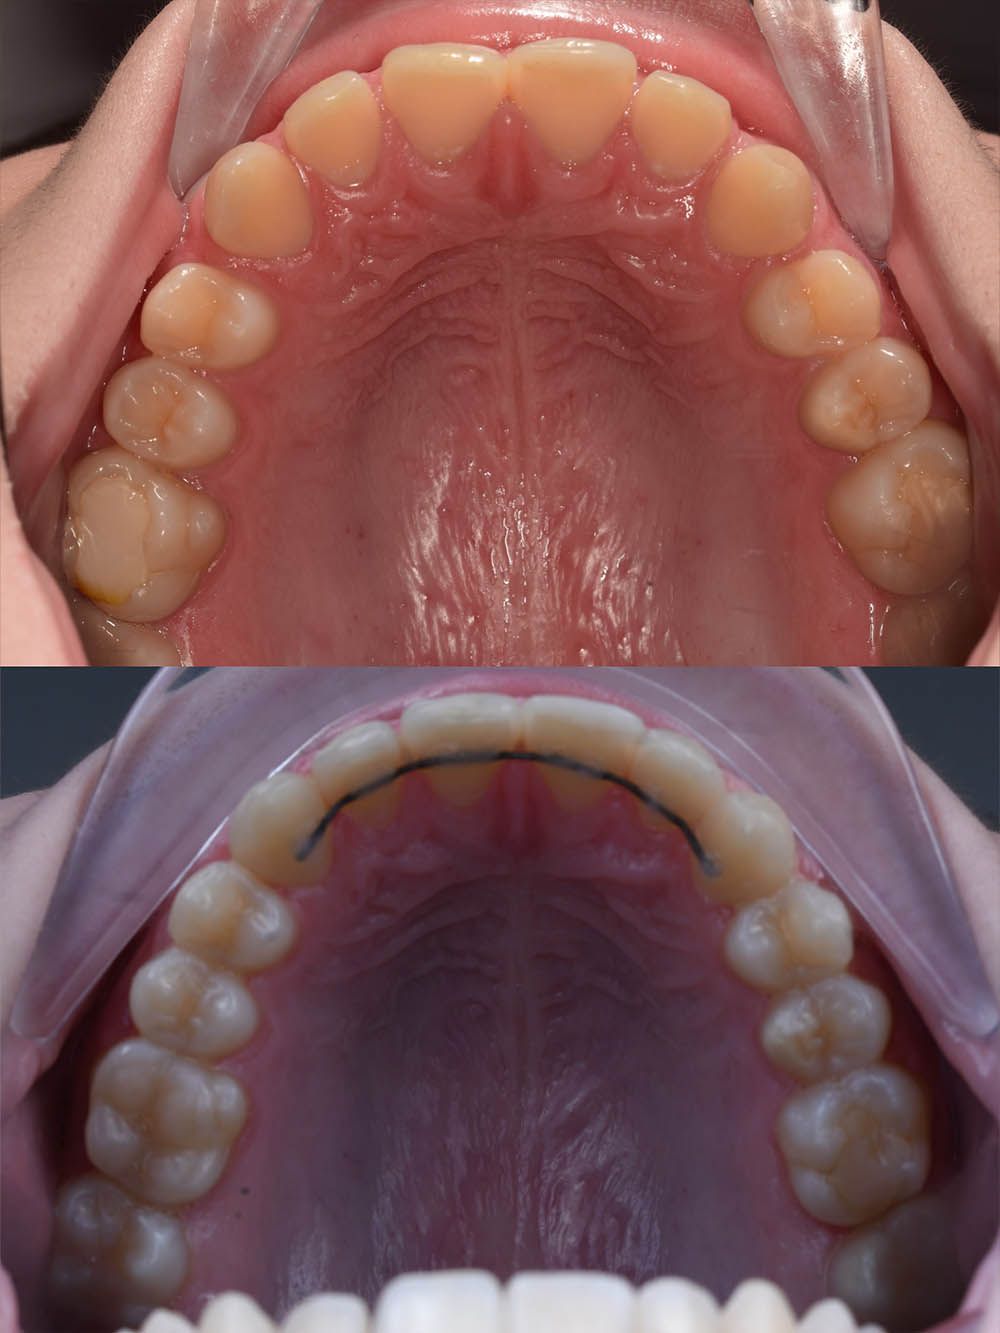

9 месяцев лечения на элайнерах

9 месяцев лечения на элайнерах

9 месяцев лечения на элайнерах